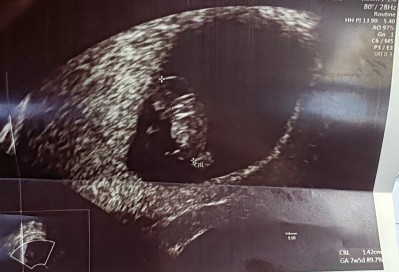

cinsiyet tahmini yapar mısınız bize ❤️